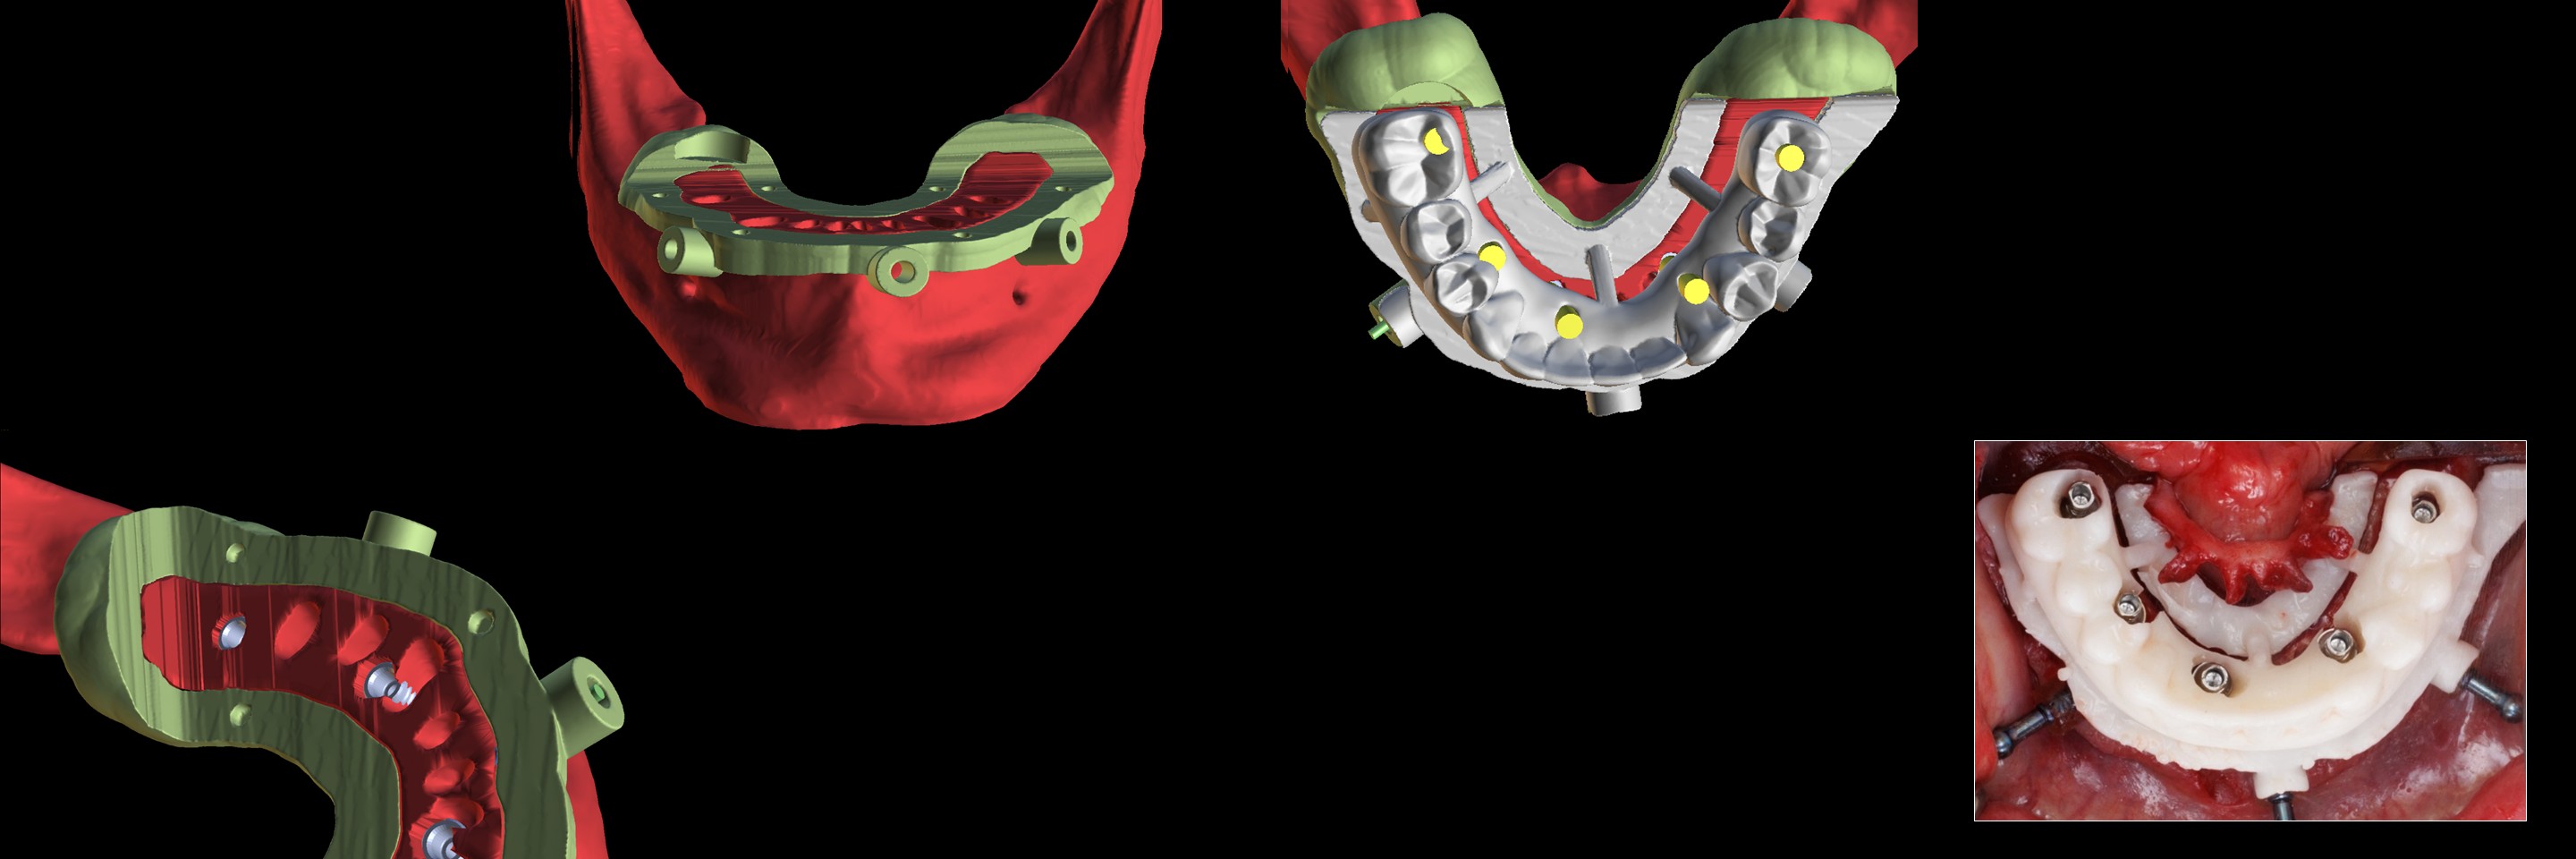

Director’s Clinical Cases

Director’s Clinical Cases